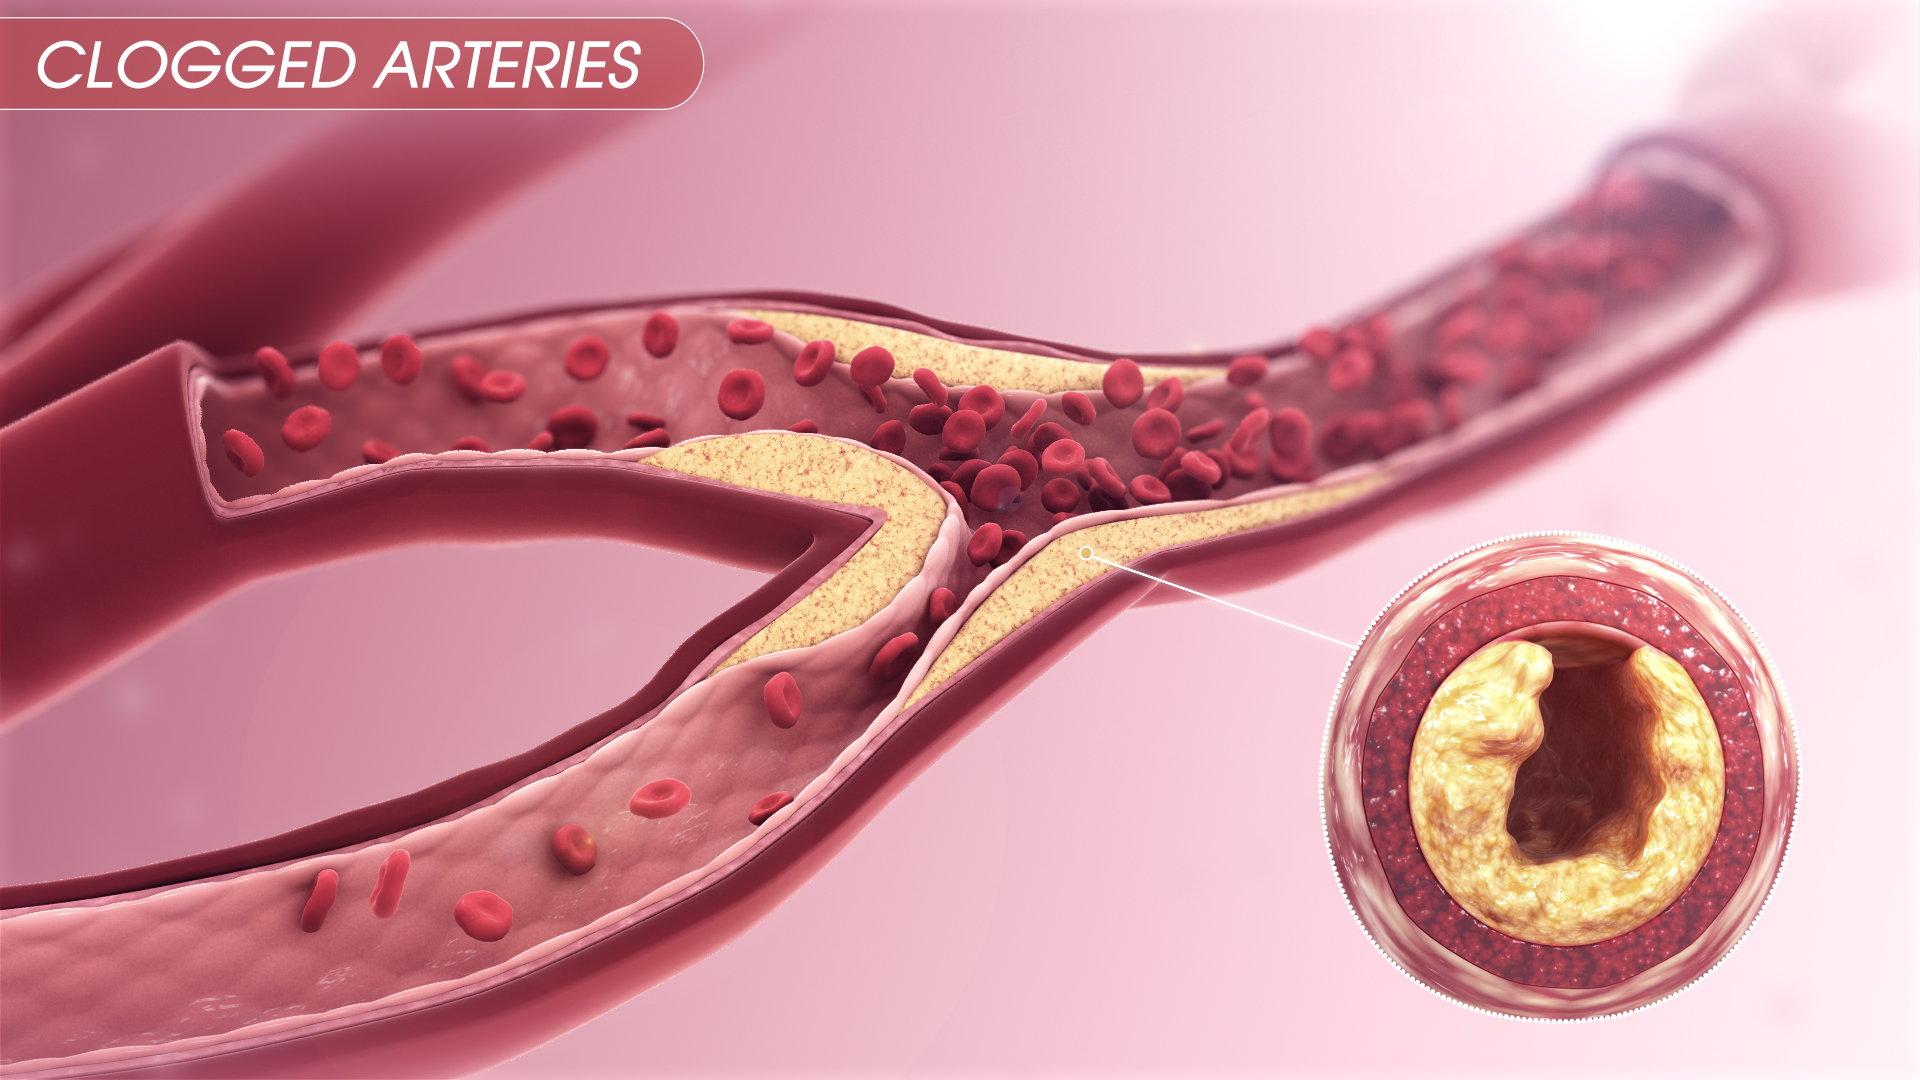

The Warning Signs Of Clogged Arteries Heart Blockage Clogged

Clogged Arteries Scientific Animations